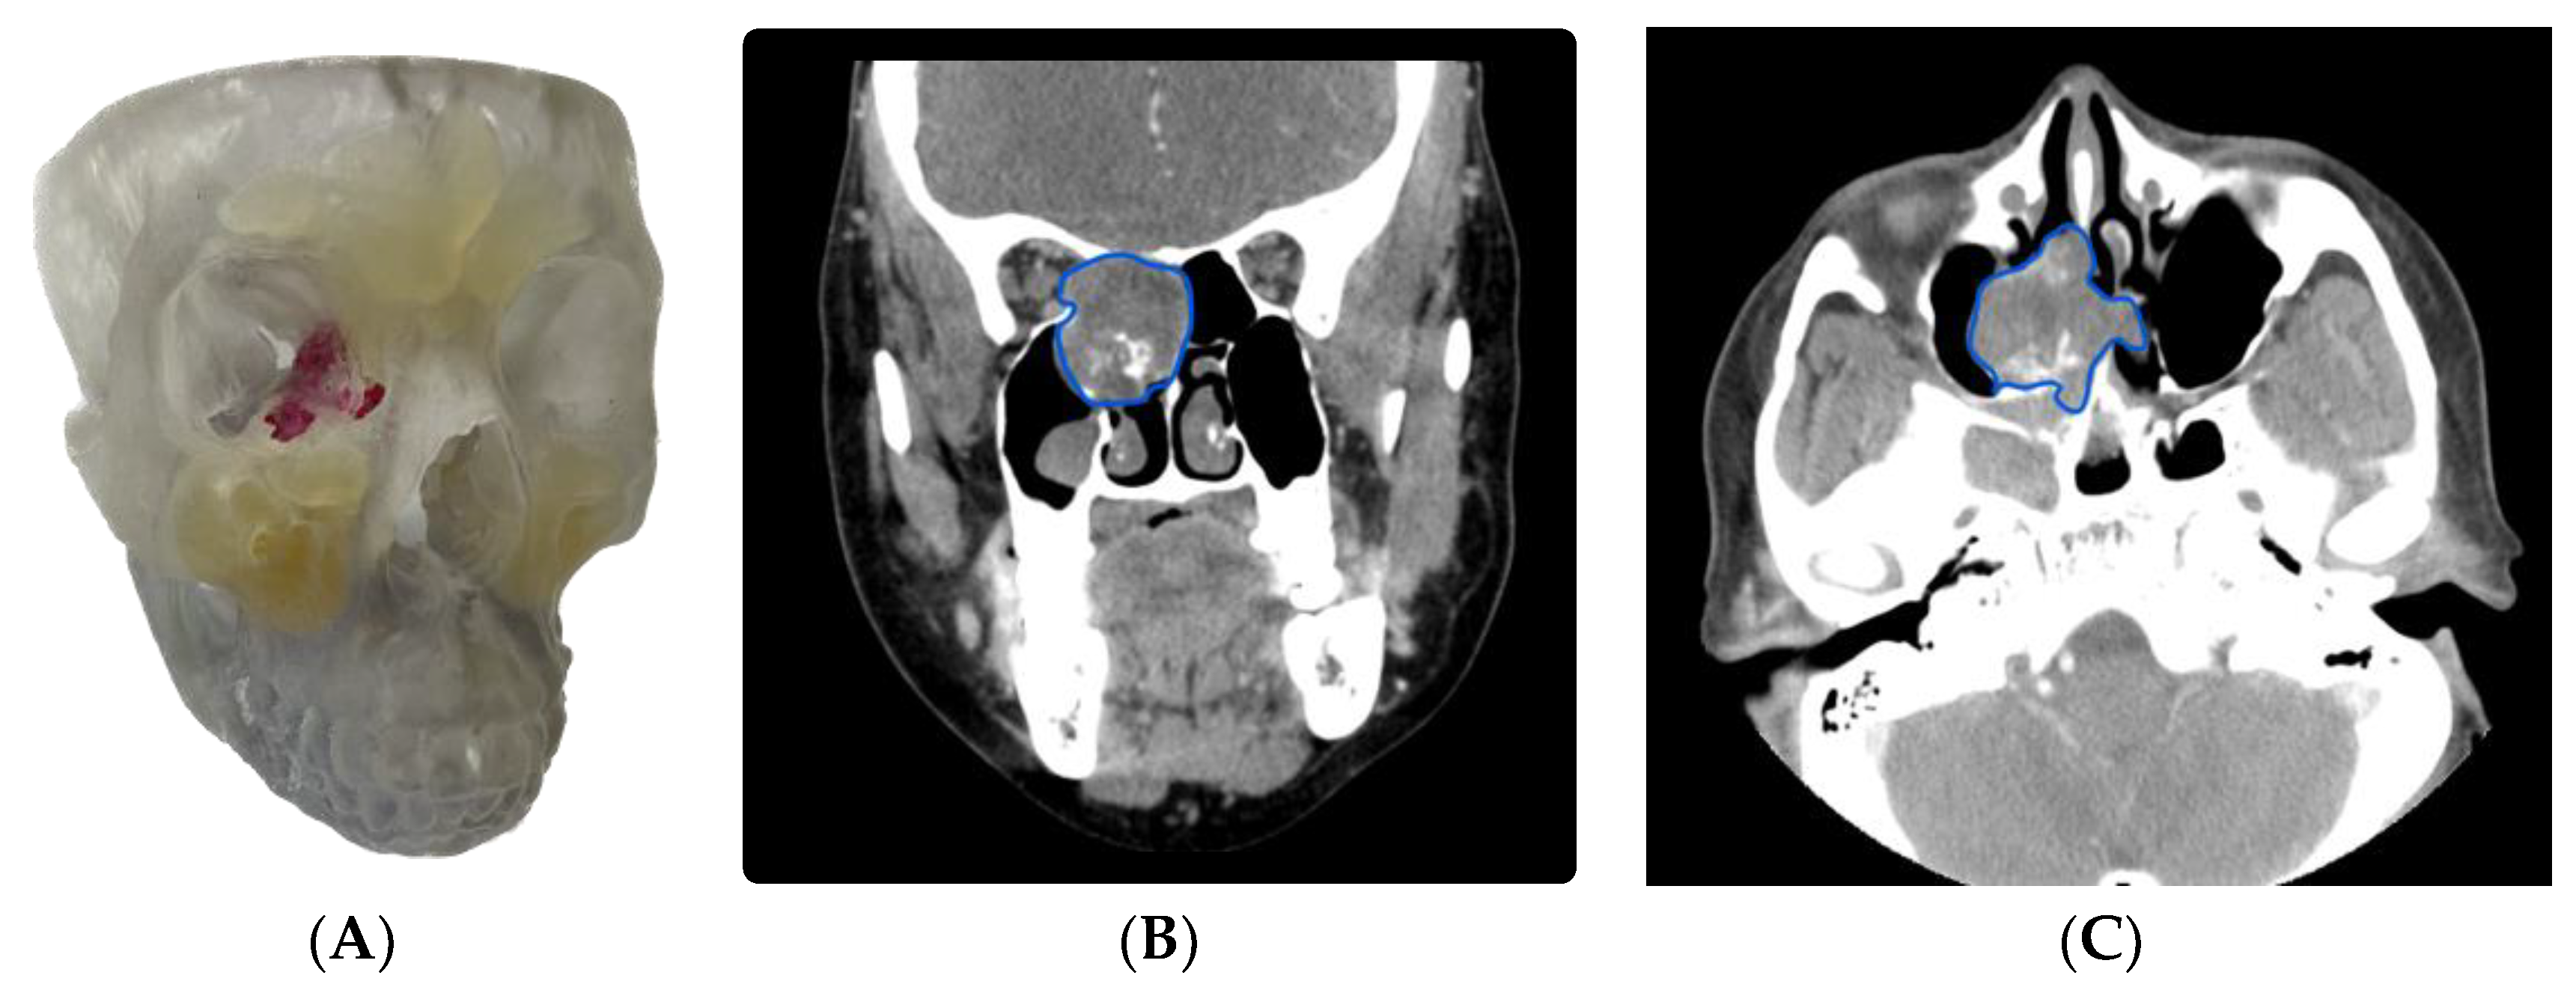

3.1.3. Case 3: Use of Virtual Surgical Planning and a 3D Model in Resident and Fellow Education